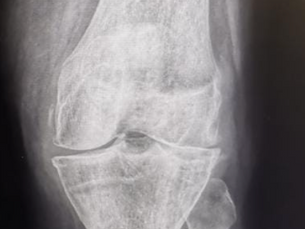

Knee Replacement

Unicondylar vs Total Knee Replacement - Pros and Cons

How to know when it is time for knee replacement surgery